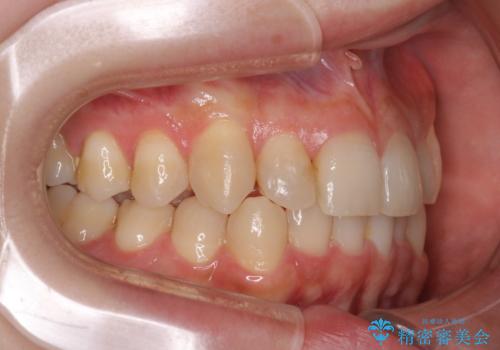

- 八重歯を治したいとのことで来院されました。

右上の犬歯が外側に飛び出して、二番目の歯が内側に入っている状態でした。

上の奥歯を後方に移動させてスペースを確保して、前歯のガタガタを改善する計画としました。

奥歯を後方に移動することで、歯を抜かずに矯正を終えることができました。